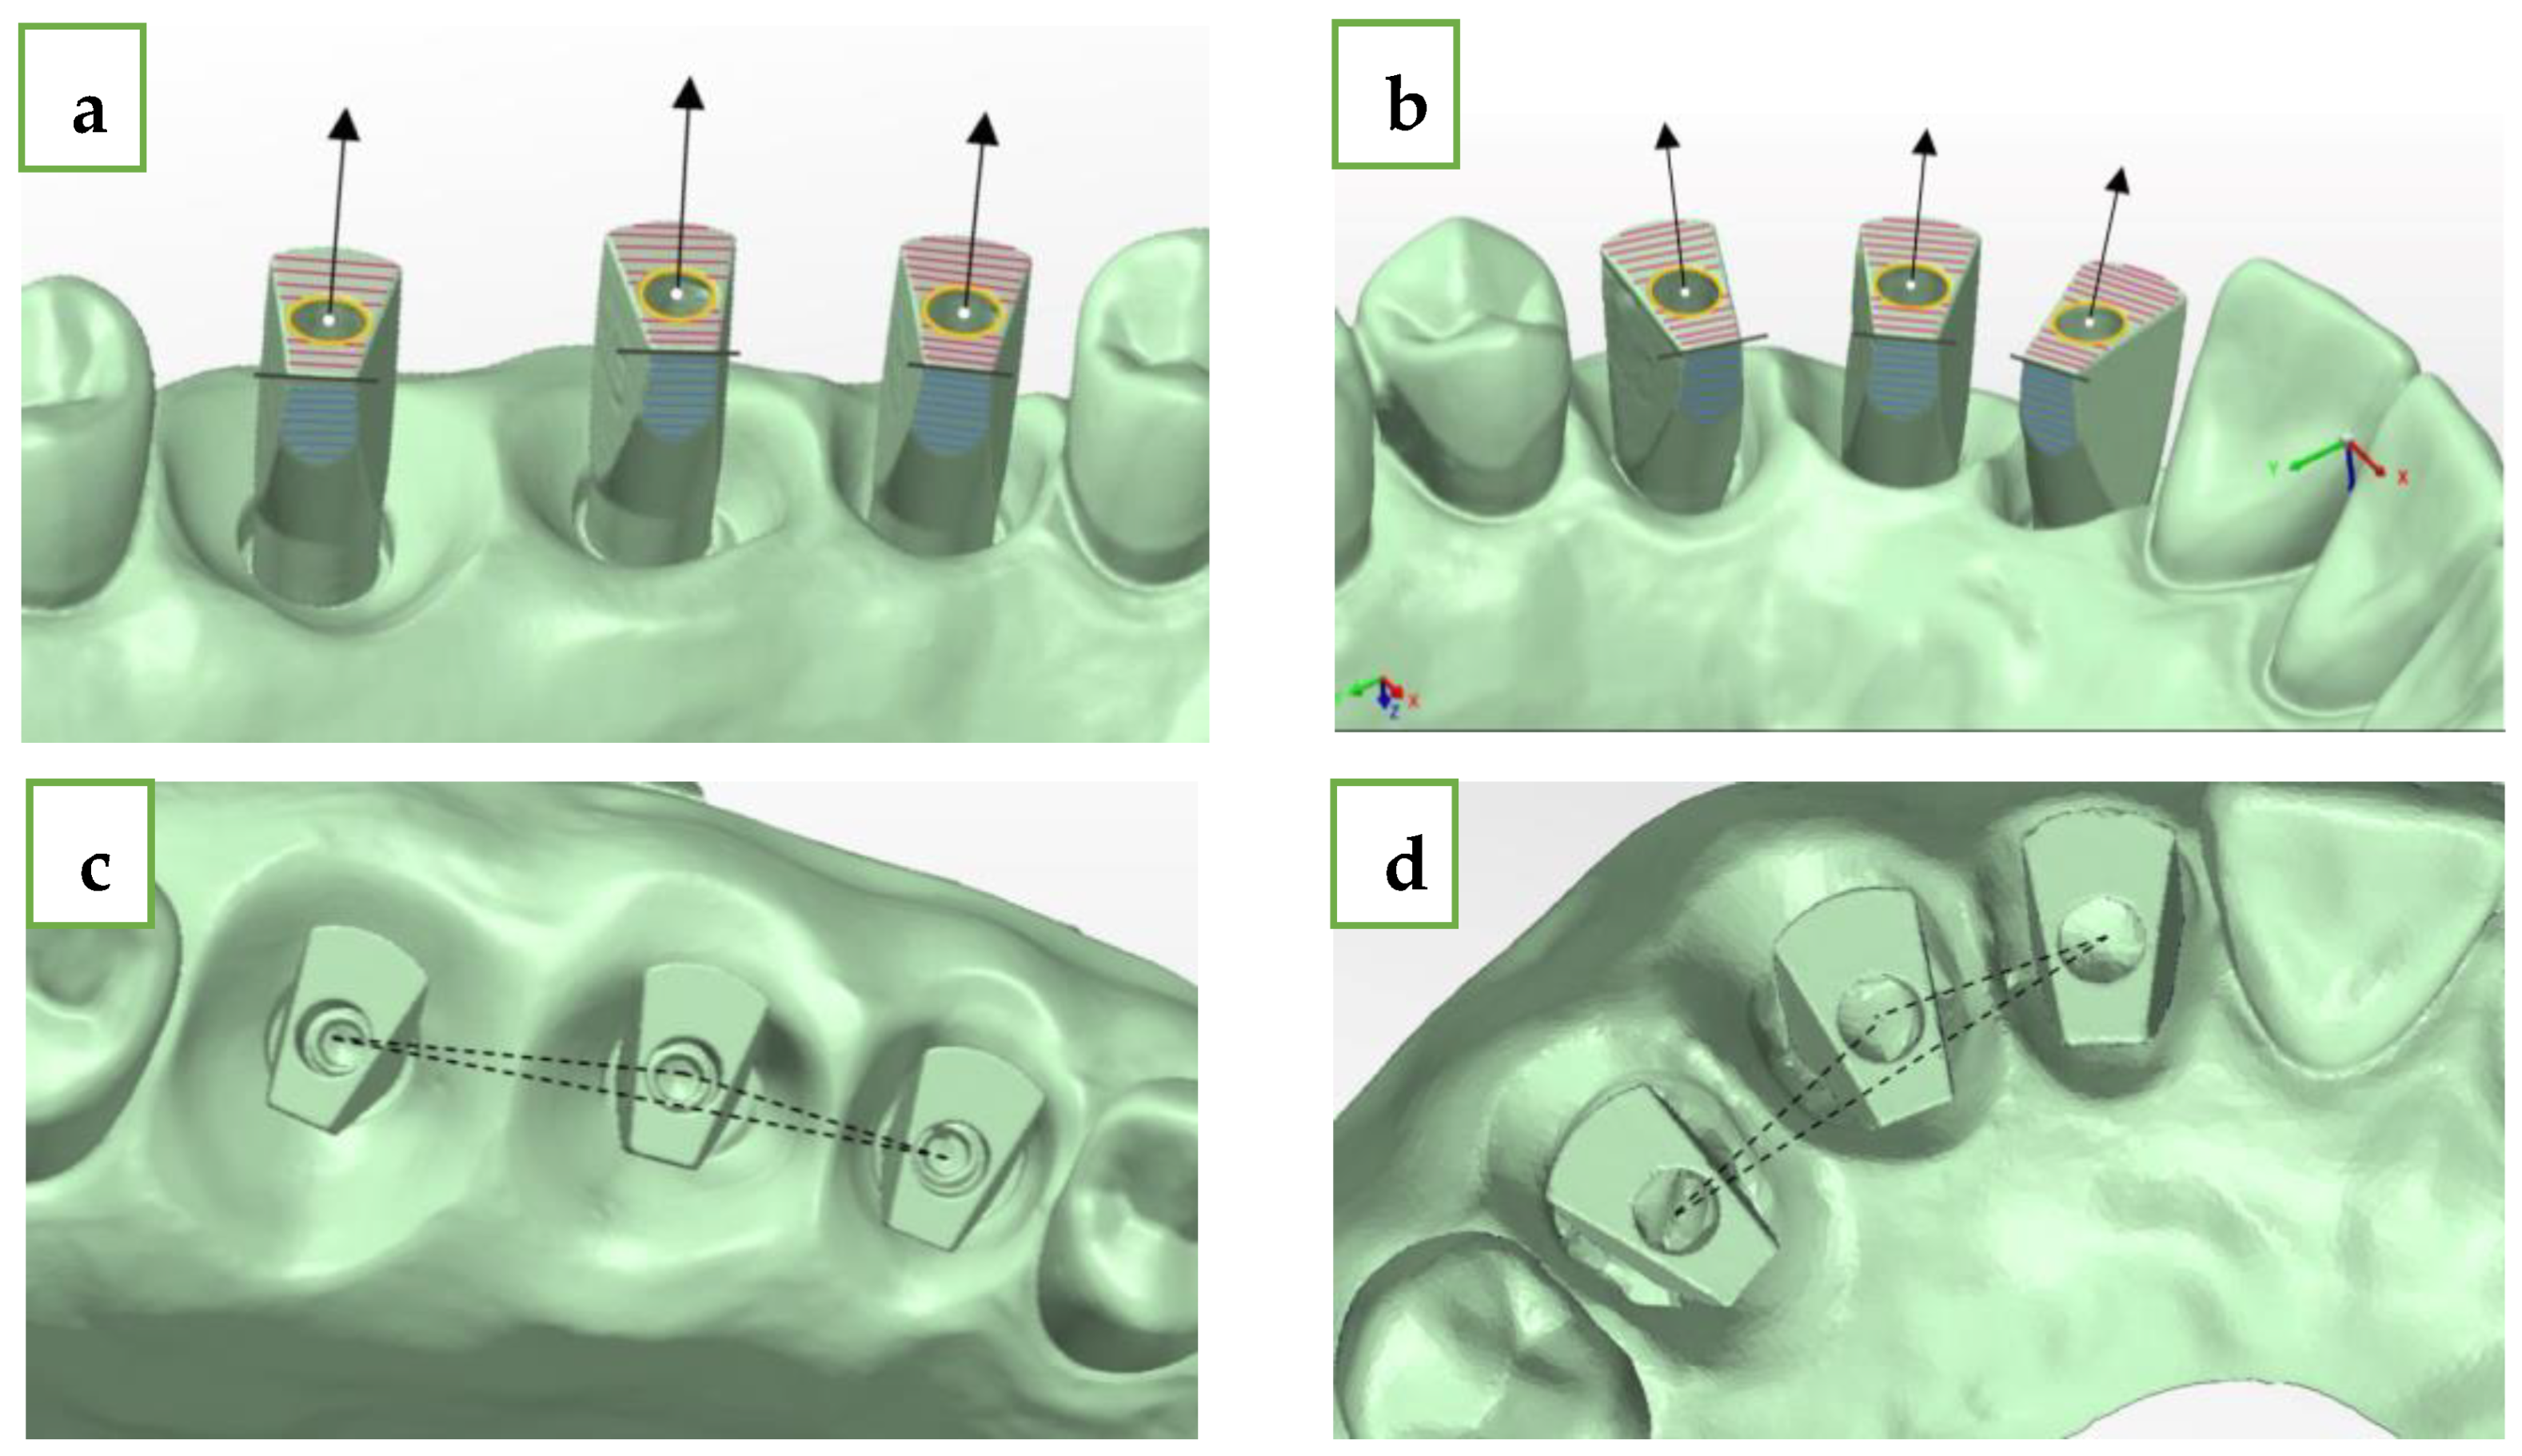

- Upper plane (red plane)—top surface of the MIS ISB, which was best-fitted;

- Cylinder (yellow circle)—inner cylinder of MIS ISB, which was best-fitted;

- Axis (black row)—longitudinal axis of MIS ISB, which was best-fitted;

- Central point (white dot)—this point is defined as the intersection between the cylinder and the upper plane of the MIS ISB;

- Palatal side plane (blue plane)—palatal straight plane of the MIS ISB, which was best-fitted;

- Sideline (black line)—this line is defined as the intersection between the upper plane and the palatal side plane for each MIS ISB;

- Inter-implant distance (black intermitted line)—the distance between two central points: distance 1–2 (#15-#16 and #12-#13), distance 2–3 (#16-#17 and #13-#14), and distance 1–3 (#15-#17 and #12-#14). The deviation of each distance from the reference model was calculated by subtraction between the two results.

- Delta axis 1–2 (green)—defined as the angle formed between the axis of the mesial (#15 and #12) and middle (#16 and #13) MIS ISB;

- Delta axis 2–3 (orange)—defined as the angle formed between the axis of the middle (#16 and #13) and distal (#17 and #14) MIS ISB;

- Delta axis 1–3 (blue)—defined as the angle formed between the axis of the mesial (#15 and #12) and distal (#17 and #14) MIS ISB.

- X-axis (red)—buccal–palatal plane; buccal is the positive direction;

- Y-axis (green)—mesial–distal plane; distal is the positive direction;

- Z-axis (blue)—occlusal–gingival plane; occlusal is the positive direction.